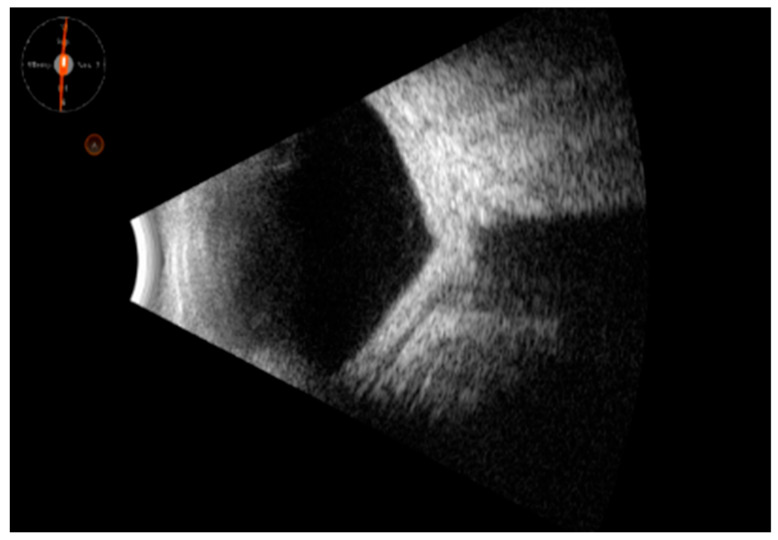

背景和目的:葡萄膜炎掩盖综合征或假面综合征(UMSs)是一组眼部疾病,有几种系统性的潜在原因,恶性或非恶性,模仿葡萄膜的炎症状态。它们通常难以用眼科检查等传统技术检测和诊断。眼部B(二维)超声(OBU)是一种无创、可重复、快速的超声方法,对导致全身性疾病的间接征象有效。其有效性与其他成像工具相当。多发性硬化的病因往往很严重,因此早期诊断和及时治疗至关重要。本研究旨在确定这些形式的超声征象,这可以帮助医生发现潜在的UMS原因。材料和方法:这是一项连续、回顾性、非随机的研究。该研究于2022年1月至2024年12月在意大利巴里大学医院综合诊所进行。共纳入186例患者,年龄从10岁到85岁不等。所有患者均行b超检查(Quantel Medical ABSolu Ocular Ultrasound)。结果:所有患者均报告视力模糊,并伴有视力下降(结论:准确诊断UMS相当具有挑战性,许多不同类型的UMS经常未被发现。这种识别的复杂性往往导致诊断不足,这意味着提高对这种疾病的认识和理解是必不可少的,以便更好地识别和治疗。及早发现这些形式是必要的。OBU的使用可以帮助早期诊断这些形式的间接迹象并及时治疗。它与其他诊断成像技术(如核磁共振成像)相比要好,但这并不意味着它取代了它们;它可以为多模态成像提供附加价值。

Background and Objectives: Uveitis-masked syndromes or masquerade syndromes (UMSs) are a group of ocular conditions with several systemic underlying causes, malignant or nonmalignant, that mimic the inflammatory status of the uvea. They are often difficult to detect and diagnose with traditional techniques, such as ophthalmic exams. Ocular B (bidimensional)-ultrasound (OBU) is a non-invasive, repeatable, rapid ultrasound method effective in indirect signs that lead back to systemic diseases. It is comparable in effectiveness with other imaging tools. The cause of UMSs can often be serious, and therefore early diagnosis and prompt treatment are critical. This study aimed to identify the sonographic signs of these forms, which can help physicians discover the cause underlying UMS. Materials and Methods: This was a consecutive, retrospective, nonrandomized study. This study was conducted at the University Hospital Polyclinic of Bari, Italy, from January 2022 to December 2024. A total of 186 patients were included, from 10 to 85 years old. They all underwent B-scan ultrasonography (Quantel Medical ABSolu Ocular Ultrasound). Results: All patients reported blurred vision, which could be accompanied by visual reduction (<20/40, Snellen charts), photophobia, floaters, flashes, proptosis, and redness. In all cases, we noted peculiar ultrasonographic signs, which allowed us to discriminate the underlying systemic diagnosis, such as vitreous corpuscles, choroid thickening, and primitive or metastatic solid tumors. Finally, we identified different diseases, such as primary intraocular lymphoma (PIOL), other lymphoproliferative conditions, orbital plasmacytoma, uveal melanoma, metastasis, endogenous endophthalmitis, retinal detachment, central serous retinopathy, metallic foreign bodies, ocular amyloidosis, and drug-induced UMSs. The sensitivity and specificity of ocular ultrasound compared to multimodal ocular imaging in UMSs were as follows: for primary intraocular lymphoma (PIOL) and other lymphoproliferative conditions, 0.98 (95% CI, 0.80-1) and 0.68 (90% CI, 0.40-0.92), respectively; for orbital plasmacytoma, 0.64 (92% CI, 0.52-0.86) and 0.66 (93% CI, 0.48-0.89), respectively; uveal melanoma, 1.00 (98% CI, 0.88-1.00) and 0.98 (95% CI, 0.86-0.98), respectively; metastasis, 0.75 (95% CI, 0.53-0.85) and 0.85 (95% CI, 0.48-0.98), respectively; endogenous endophthalmitis, 1.00 (95% CI, 0.50-1.00) and 0.83 (95% CI, 0.48-0.98), respectively; retinal detachment, both were 1.00 (95% CI, 0.87-1.00 and 0.84-0.97, respectively); central serous retinopathy, 0.60 (80% CI, 0.41-0.88) and 0.85 (95% CI, 0.52-0.98), respectively; metallic foreign bodies, 1.00 (95% CI, 0.78-1.00) and 0.99 (95% CI, 0.99-1.00), respectively; ocular amyloidosis, 0.77 (82% CI, 0.52-0.90) and 0.83 (80% CI, 0.49-0.88), respectively; and drug-induced UMSs, 0.64 (95% CI, 0.49-0.88) and 0.85 (95% CI, 0.52-0.98), respectively. Conclusions: Diagnosing UMS accurately can be quite challenging, and many of its different types frequently go undetected. This complexity in identification often leads to underdiagnosis, meaning it is essential to improve awareness and understanding of the condition in order to achieve better recognition and treatment. Early detection of these forms is imperative. The use of OBU can help diagnose indirect signs of these forms early and treat them promptly. It compares well with other diagnostic imaging techniques, such as MRI, but this does not mean that it replaces them; it can offer added value in multimodal imaging.